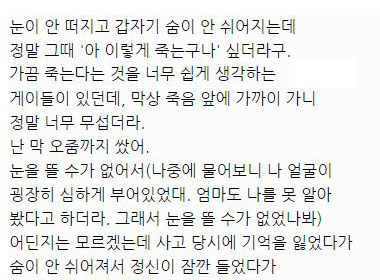

아래는 해당 글 작성자가 쓴 글.

대단한 얘기는 아니지만 중환자실에 3주동안 무의식으로 있었던 썰 풀어볼게